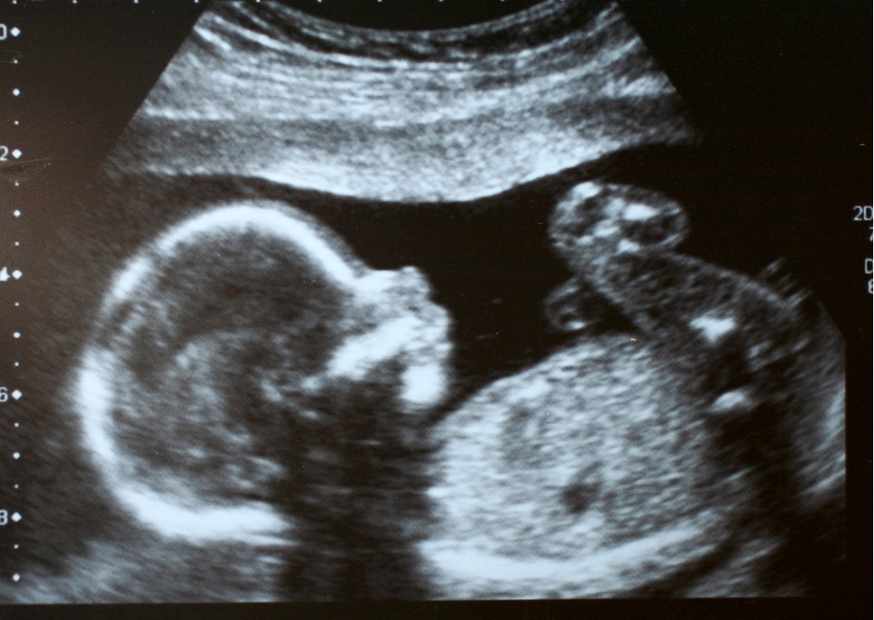

تحفز الإبرة التفجيرية الاباضة في خلال 48 ساعة من الحصول عليها، ويظهر الحمل في عينة الدم في خلال 10 إلى 14 يوماً من تناولها، وفي ذاك يفضل إجراء اختبار الحمل بالدم أفضل من اختبار الحمل المنزلي، حتى لا تحدث نتيجة إيجابية خاطئة بسبب الهرمونات، فاختبار الحمل عن طريق الدم هو أدق في قياس الهرمونات بالجسم، الكثير من حالات الحمل بعد الإبرة التفجيرية هي حالات ناجحة والإجهاض بعدها ليس هو الشائع فلا تخافي بعد الإبرة فمن المهم ان تكون حالتك النفسية جيدة.

تسأل إحدى السيدات عن موعد نزول الدورة الشهرية بعد الإجهاض الناتج عن الإبرة التفجيرية، وكان رد الطبيب عليها هو أن نزول الدورة الشهرية يكون بعد شهر من الإجهاض، ولكن عليها زيارة الطبيب للفحص والمتابعة بالسونار للتأكد من نظافة الرحم وعدم الحاجة إلى أدوية أخرى.